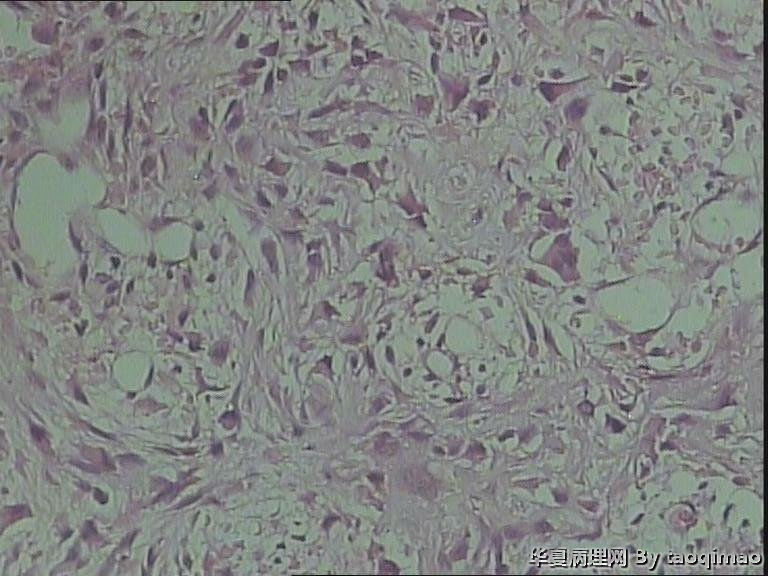

• 肋骨肿物,求助图4

图4

这是一部分容易取下来的肿瘤,其余部分还在脱钙中

患者女,31岁,胸部CT第八肋骨肿瘤,肿物在肋骨内突出骨外膜,大小2.3X1.5.切面灰白质韧

骨母细胞瘤。矿化不均要除外骨母细胞型骨肉瘤,虽然肿块小了点。还是找找核分裂,看看X线的好。